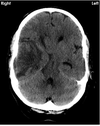

Describe the CT

Extra-axial cresent shaped fluid collection over the right cerebral convexity (A,B) indiacting chronic SDH

As patient is supine, there is layering according to density, wthi hypodense fluid supernatant (A) above hyperdense thrombus or cellular precipitant.

This could be due to a single episode of heamorrhage or rebleeding into a chronic collection.

There is midline shift (C) with obliteration of cerebral sulci and the trigone not seen on the right